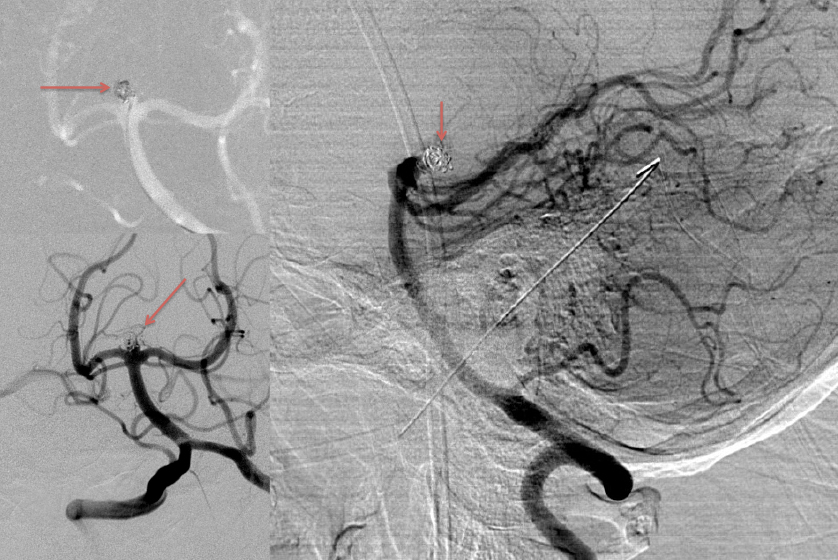

A man in his 40’s experienced an acute onset of a moderate headache. Over the next 3 days, his family noticed increased lethargy, decreased appetite, and gait imbalance, which prompted them to bring him to the ED for evaluation. Initial CT scan of the brain confirmed diffuse subarachnoid hemorrhage with hydrocephalous, which required emergent EndoVentricular Drainage for a progressive diminished level of consciousness, WFNS Grade 3-4 (Figure 1).

Figure 1: Non-Contrast CT of the Brain demonstrates diffuse subarachnoid hemorrhage(red) and early dilatation of the temporal horns consistent with hydrocephalous (yellow).